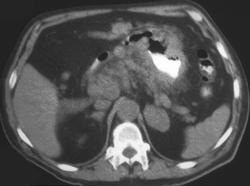

Diagnosis

Gastric Adenocarcinoma